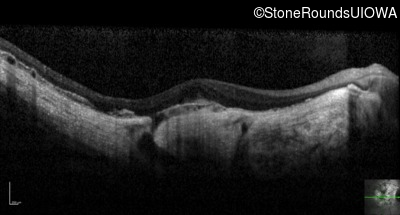

Optical Coherence Tomography - Left - 20/25 -2

Exemplar / OCT Stack